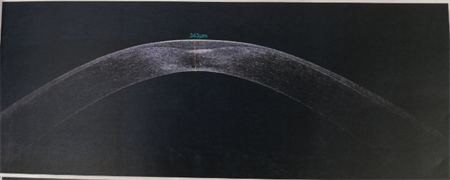

商旭敏副主任告訴我們,小蕓的右眼已經(jīng)是圓錐角膜后期,角膜厚度僅有343,再繼續(xù)發(fā)展下去,就會(huì)水腫破裂。由于圓錐角膜都是雙眼發(fā)病,小蕓的左眼此時(shí)也開(kāi)始出現(xiàn)圓錐角膜的癥狀了。

▲小蕓右眼厚度343,左眼厚度523